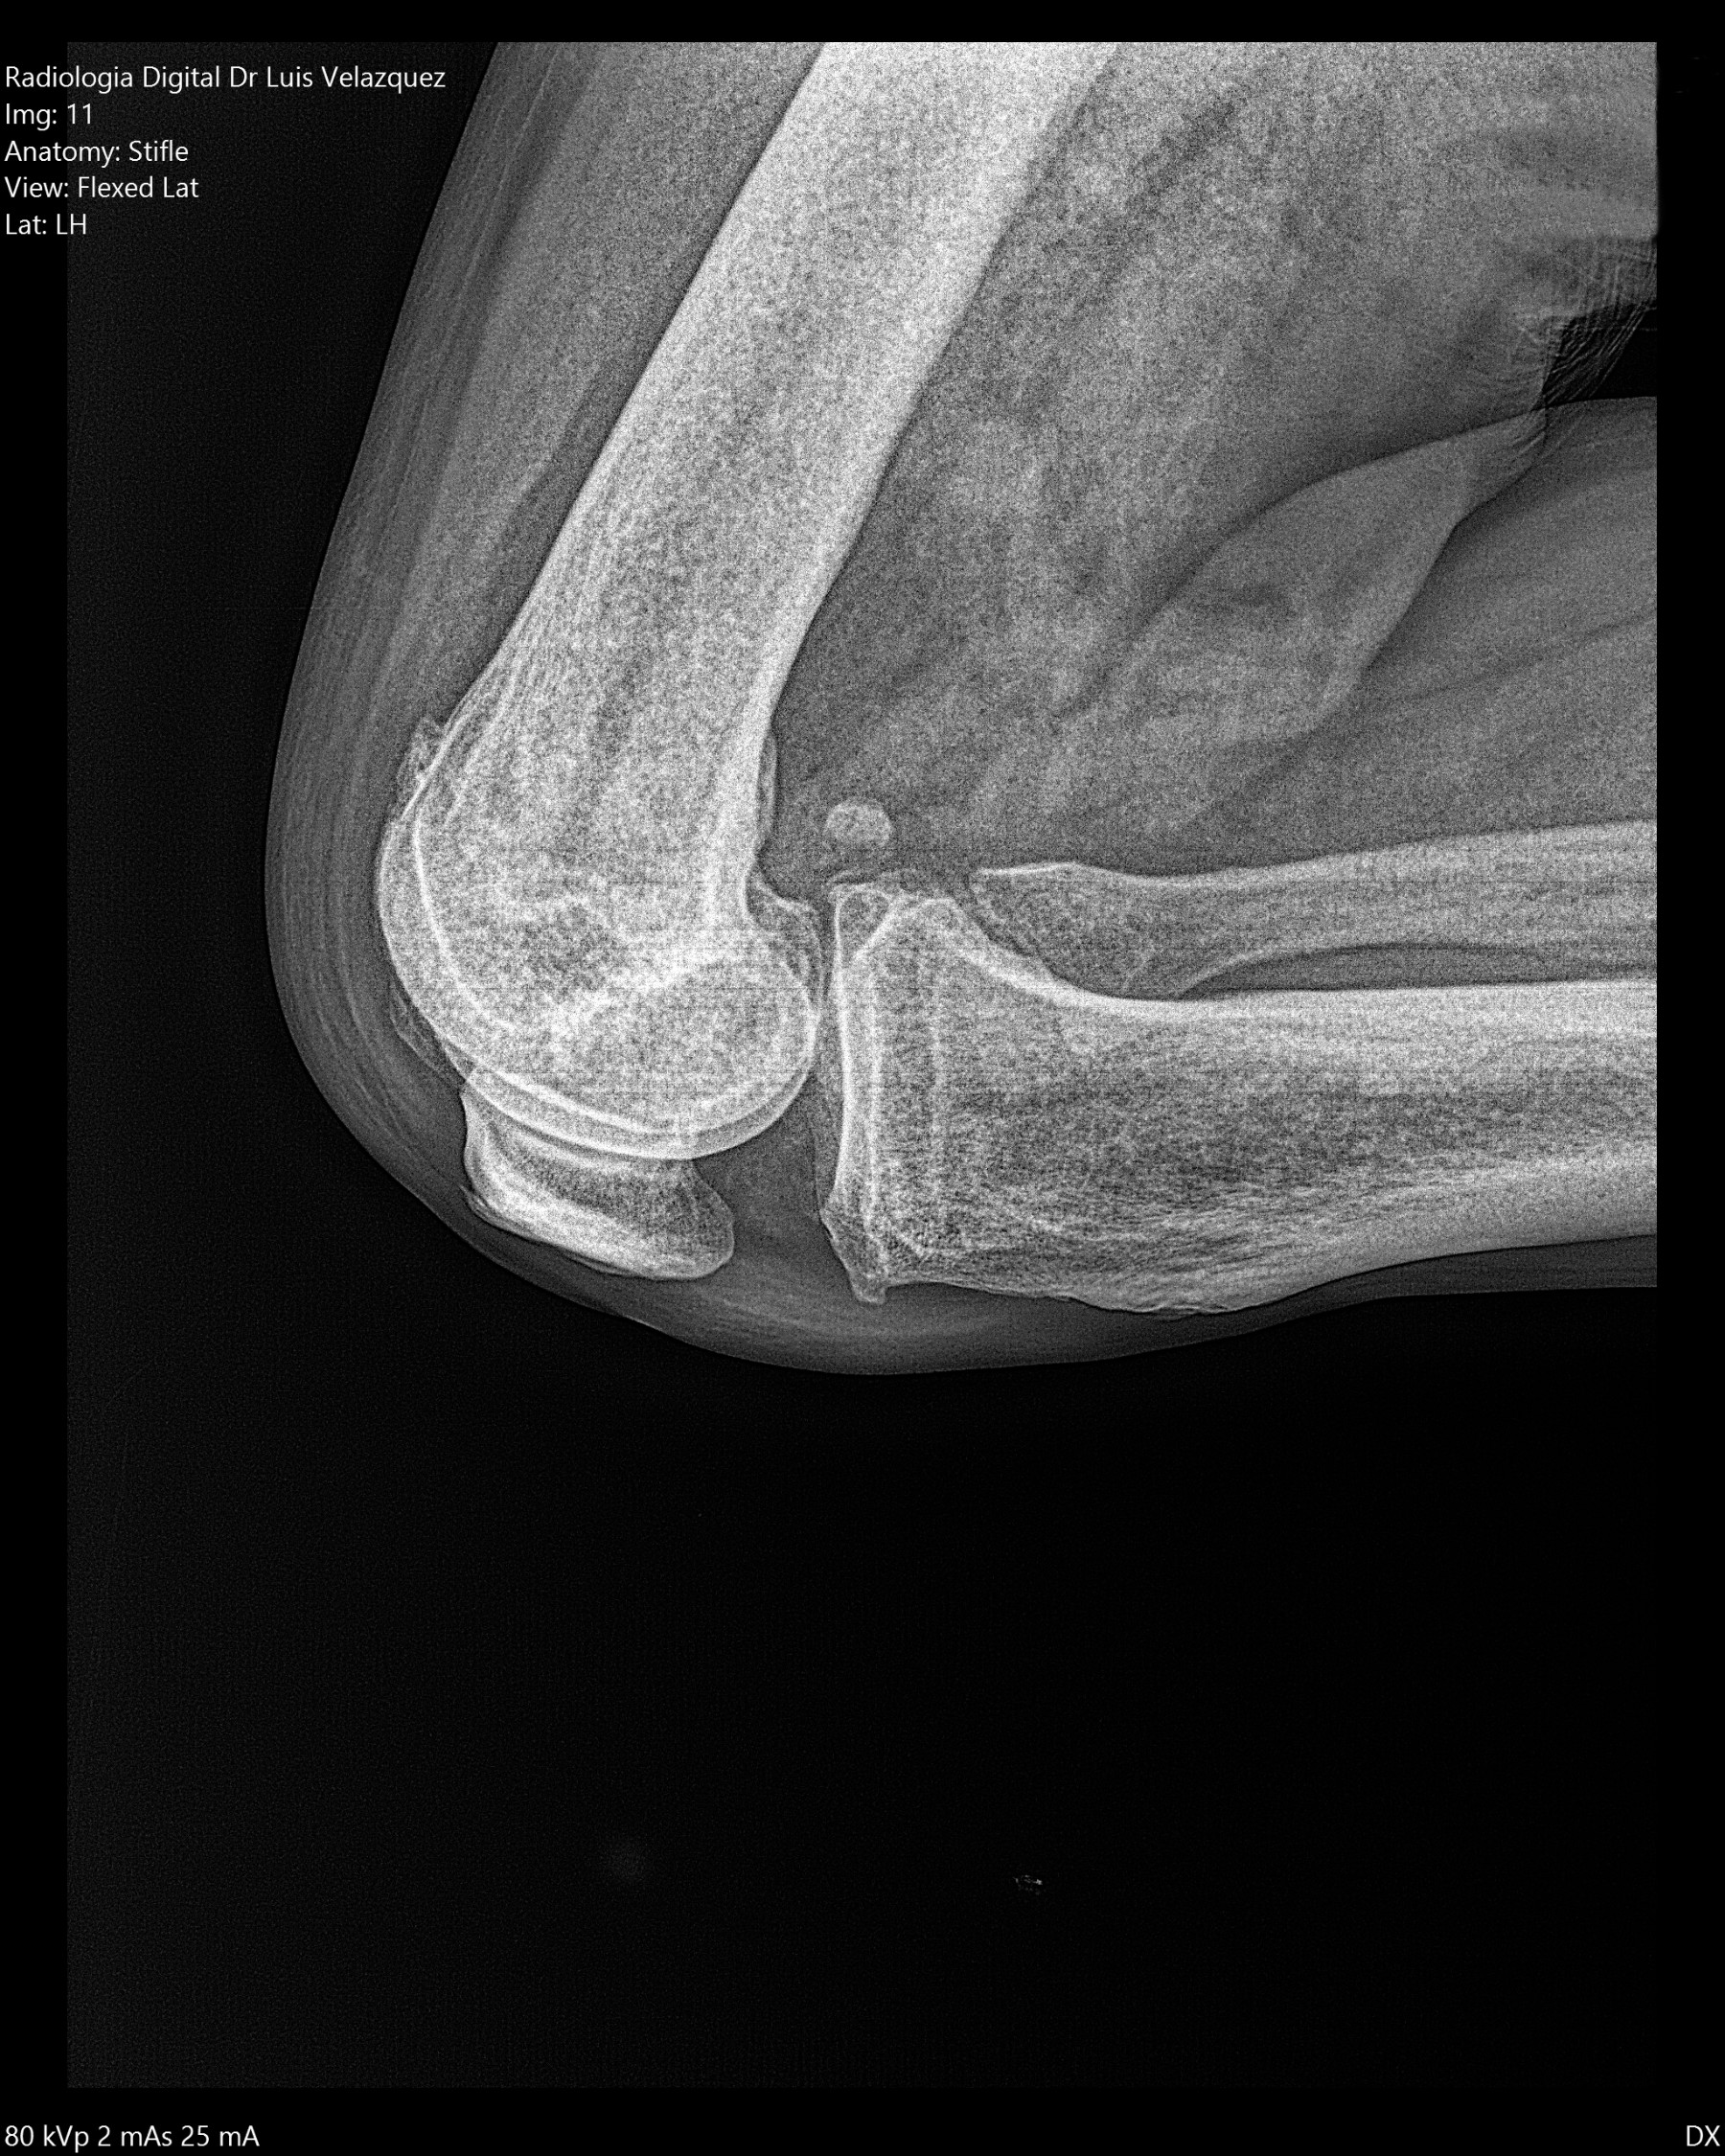

Radiología Digital como Herramienta Complementaria en el Dictamen de Bienes Muebles

Cambios Térmicos en las Extremidades de Caballos,

Asociados a Golpes y su Evaluación por Termografía.

Los caballos de salto, en competencia, pueden derribar obstáculos y lastimarse. Si se golpean, no siempre claudican. Considerando al calor como un signo de inflamación, se evaluaron los cambios térmicos de 6 áreas de las extremidades torácicas y pelvianas de 23 caballos de salto en nivel de competencia de 1.05 a 1.60 m de altura, por medio de termografía durante 4 días de competencia (N=2208 áreas).